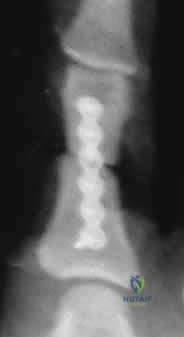

3. التثبيت داخل النقي (Intramedullary Fixation):

تُستخدم هذه التقنية الحديثة لبعض الكسور العرضية في السلاميات، حيث يتم إدخال سلك أو مسمار دقيق داخل التجويف العظمي (النقي). توفر هذه الطريقة ثباتاً جيداً دون التأثير على الأنسجة الرخوة المحيطة بالعظم.